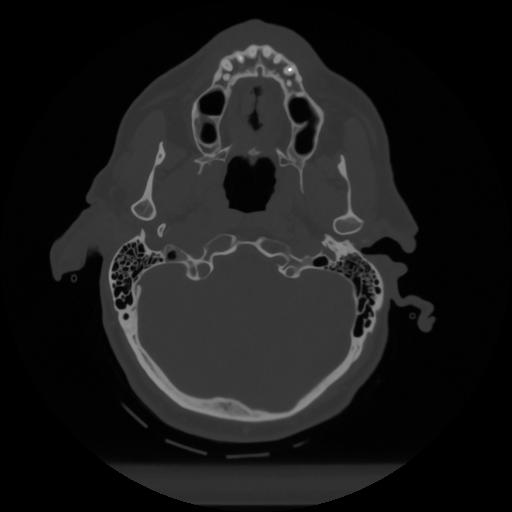

12 P.BLANDAS,,Vol,0.5,P.BLANDAS,,